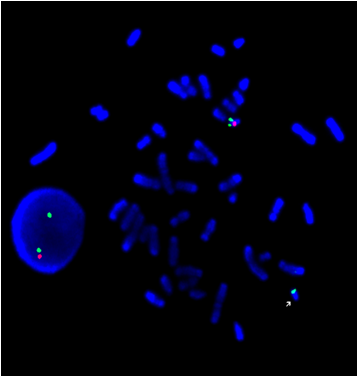

www.hamiltonhealthsciences.ca

PDGFRB FISH Product Datasheet

10 pages